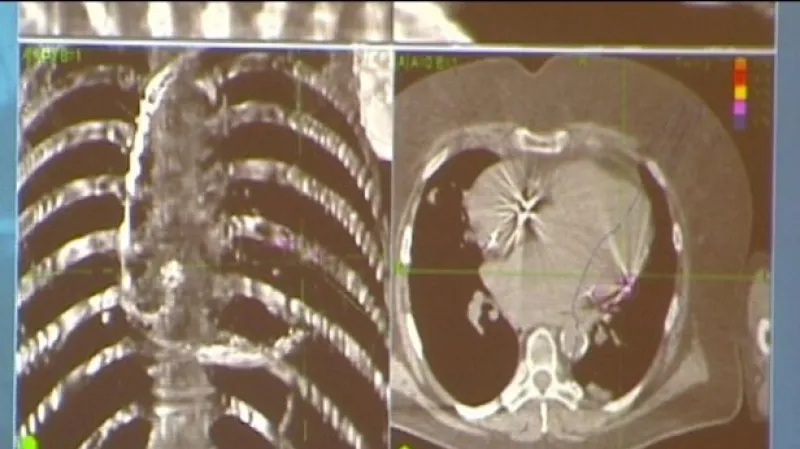

Na nápad použít v jejím případě CyberKnife přišel kardiolog z Třince Radek Neuwirth, který ženu léčil. S kolegy zkoušel nejprve speciální defibrilátor. Ten sice dokáže arytmii ukončit, ale za cenu velkých bolestí. Poté naordinoval léky - antiarytmika, ale ty selhaly. „Našli jsme přesně ložisko, které arytmii spouští, a snažili jsme se ho odstranit, ale to se nám nepodařilo,“ popsal Neuwirth léčbu, které předcházela funkční radiochirurgii s využitím CyberKnifu.

„Pustíte obrovskou dávku záření do malinkého cíle někde v těle. Normálně se to používá proti nádorům, ale umí to likvidovat i jiné cíle, třeba shluky buněk, které jsou centrem nějakého vzruchu nebo funkce,“ vysvětloval přednosta Onkologické kliniky Fakultní nemocnice v Ostravě David Feltl. Prohlásil, že podobným způsobem před nimi použili CyberKnife pouze lékaři v Americe. „Ostravský případ je ale první s doloženou účinností,“ zdůraznil přednosta.